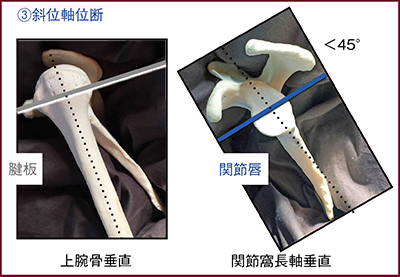

肩関節撮像の上級者を目指すには,2方向での位置決めを極めてほしい。例えば,不安定肩(Bankart損傷,Hill-Sachs損傷)やスポーツ障害肩(SLAP障害)は,関節窩に対して垂直の軸位断を撮像することで,関節唇を明瞭にとらえることができる。考え方としては,肩甲骨の直交3方向を考えて新しい座標軸をつくるが,読影医からすると回転しているように見えるため,回転補正をかけて画像を表示する必要がある。2方向位置決め撮像においても,斜位冠状断の基準線は,肩甲骨平面と上腕骨頭の長軸をつないだ線となる。また,斜位軸位断は,腱板断裂の評価では上腕骨に垂直,関節唇の評価では関節窩長軸に垂直の断面を撮像する(図2)。なお,肩甲骨平面と上腕骨頭長軸は完全に合わせる必要はないが,角度を可能な範囲で浅くすることが望ましい。

患者固定においては,半側臥位とすることで静磁場中心にポジショニングでき,画質が向上し,脂肪抑制も良好となる。また,肩甲骨をフラットに寝台に置くことになるため,モーションアーチファクトも抑制できる。固定では患側を下にするため,対側の肩の下にパッドを入れ,疼痛を誘発しない程度にするのがよい。また,斜位矢状断については,筋萎縮や関節唇損傷を正しく表示するために,関節窩に平行の断面像であることが望ましい。しばしば上腕骨に平行の断面像を見るが,腱板断裂の評価には不適切である。一方,不安定肩やスポーツ障害肩の斜位軸位断は,関節窩に垂直に撮像するため,何度か回転補正をして表示する必要がある。

図2 腱板と関節唇を評価するための斜位軸位断